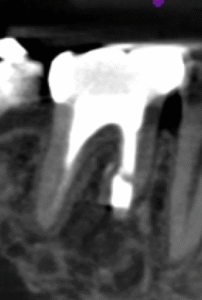

術後にPA, CBCTを撮影した。

外科治療をしているので歯槽骨の欠損が大きい。

が、この患者さんは歯周病でない。

ということは…治癒する余地がある。